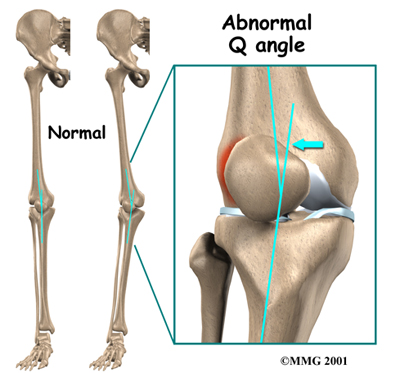

Another type of imbalance may exist due to differences in how the bones of the knee are shaped. These differences, or anatomic variations, are something people are born with. Some people are born with a greater than normal angle where the femur and the tibia (shinbone) come together at the knee joint. Women tend to have a greater angle here than men. The patella normally sits at the center of this angle within the femoral groove. When the quadriceps muscle contracts, the angle in the knee straightens, pushing the patella to the outside of the knee. In cases where this angle is increased, the patella tends to shift outward with greater pressure. This leads to a similar problem as that described above. As the patella slides through the groove, it shifts to the outside. This places more pressure on one side than the other, leading to damage to the underlying articular cartilage.

Another type of imbalance may exist due to differences in how the bones of the knee are shaped. These differences, or anatomic variations, are something people are born with. Some people are born with a greater than normal angle where the femur and the tibia (shinbone) come together at the knee joint. Women tend to have a greater angle here than men. The patella normally sits at the center of this angle within the femoral groove. When the quadriceps muscle contracts, the angle in the knee straightens, pushing the patella to the outside of the knee. In cases where this angle is increased, the patella tends to shift outward with greater pressure. This leads to a similar problem as that described above. As the patella slides through the groove, it shifts to the outside. This places more pressure on one side than the other, leading to damage to the underlying articular cartilage.